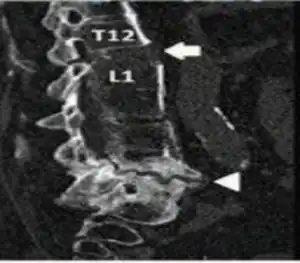

Chalkstick fractures are particularly common in Paget's disease of bone, and osteopetrosis.[2] It is also seen in cases of fused spine as in a patient with ankylosing spondylitis.[3]